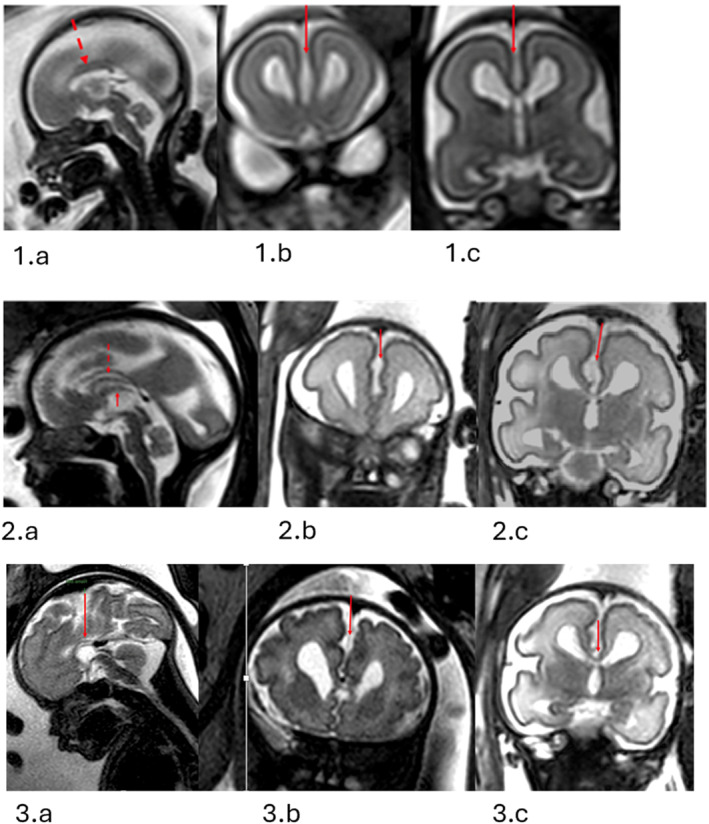

Case presentation: We report three fetuses, all with a recurrent pathogenic PPP2R1A variant (c.544C〉T, p.Arg182Trp), identified at a single fetal diagnostic service over 12 months. The neuroradiological phenotype included corpus callosum dysgenesis, widening of the interhemispheric fissure and ventriculomegaly consistent with an aqueduct stenosis pattern. Two pregnancies ended in termination; one continued, with diagnosis confirmed postnatally.

Discussion: These cases broaden the prenatal neuroradiological spectrum of PPP2R1A-rNDD and, more specifically, a missense variant associated with the p.Arg182Trp change. These cases share reduced CC length (sometimes markedly) and widening of the interhemispheric fissure as common features.